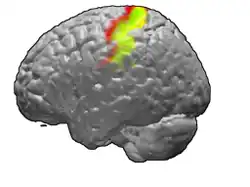

Brodmann areas 3, 1 and 2 of human brain. Brodmann area 3 is in red, area 1 in green, and area 2 in yellow.

The primary somatosensory cortex was initially defined from surface stimulation studies of Wilder Penfield, and parallel surface potential studies of Bard, Woolsey, and Marshall. Although initially defined to be roughly the same as Brodmann areas 3, 1 and 2, more recent work by Kaas has suggested that for homogeny with other sensory fields only area 3 should be referred to as "primary somatosensory cortex", as it receives the bulk of the thalamocortical projections from the sensory input fields.

The postcentral gyrus includes Brodmann areas 1, 2, and 3. Brodmann area 1 occupies the apex of the postcentral gyrus.